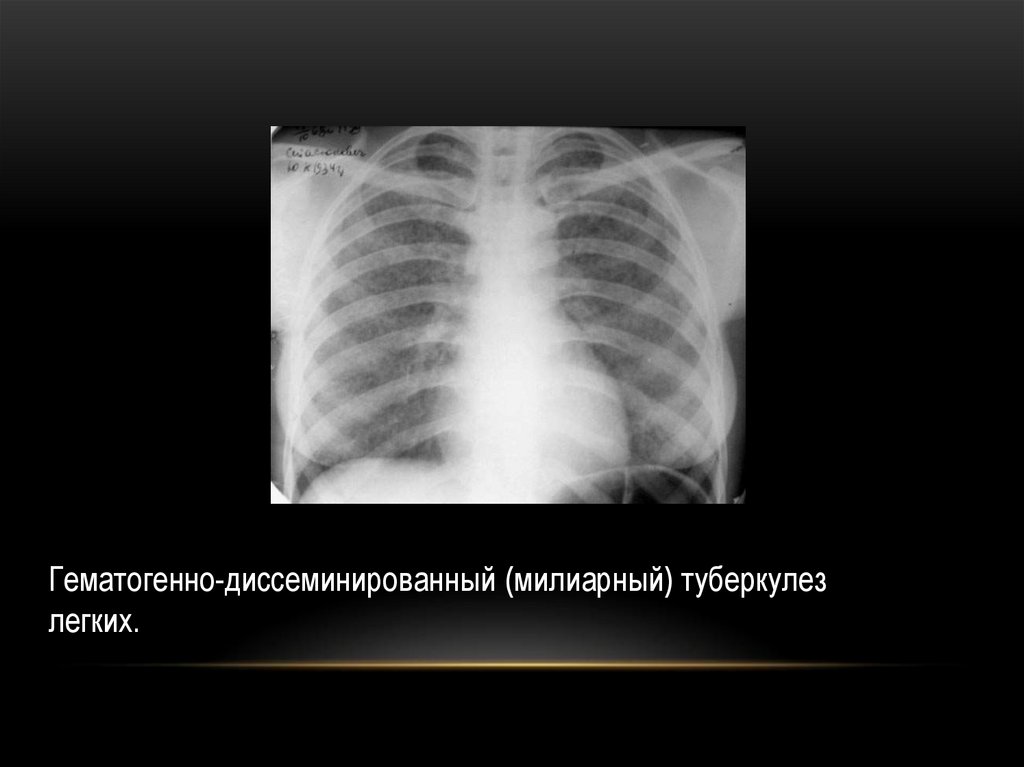

Гематогенно-диссеминированный (милиарный) туберкулез

легких.